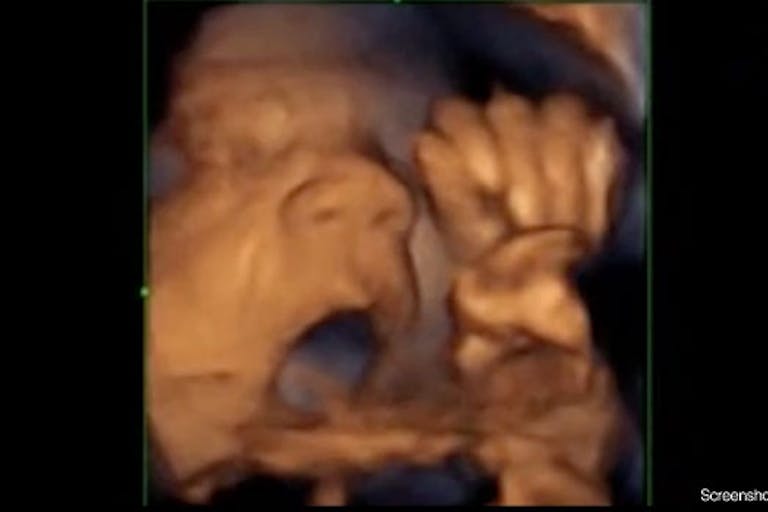

In its 2015 study, the Institut captured preborn babies appearing to sing along to music when they heard it. This trend continued in the most recent study:

As the researchers observed the babies’ facial expressions and the movement of their tongues, the children’s musical preferences were quite stark. The study results state that babies were stimulated by “neither pop nor rock” and that “the same as newborn babies, [these children] prefer classic music to traditional music.” Mozart’s “A Little Night Music” and a Spanish Christmas carol ranked at the top of their categories. Queens’ “Bohemian Rhapsody” and the popular “Y.M.C.A.” were two exceptions to the general preference against pop and rock. Adele, while very popular with parents, was not so popular among their tiny offspring.